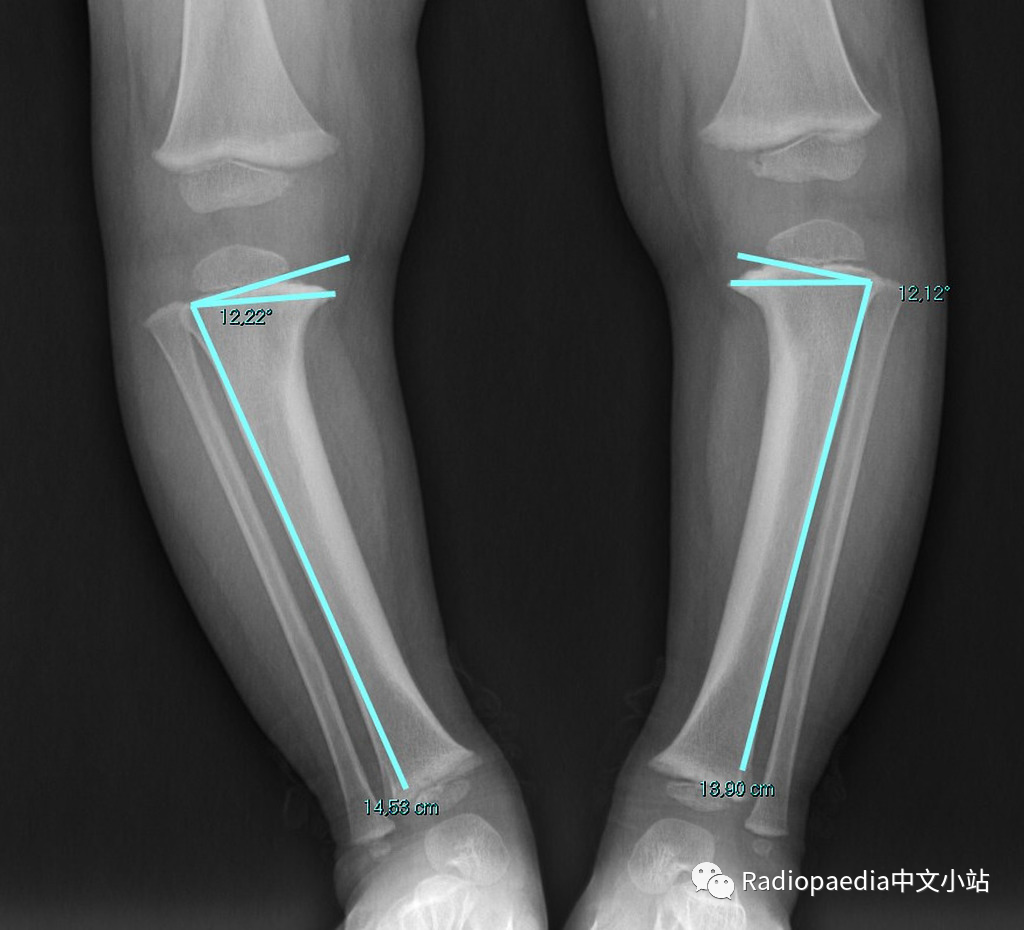

胫骨干骺端-骨干角

胫骨干骺端-骨干角:通过胫骨近侧干端的最宽处画条直线(连接内侧和外侧尖状突起处),该线与胫骨长轴的垂直线形成的角度,用于诊断Blount病。胫骨生理性弯曲(2岁以下常见)时,这个角度大约为5°,当大于11°提示 Blount病,大于20°可确诊。但是,一些研究已经开始质疑干骺端-骨干角的有效性,因为该角度的测量可能受到胫骨旋转的影响。